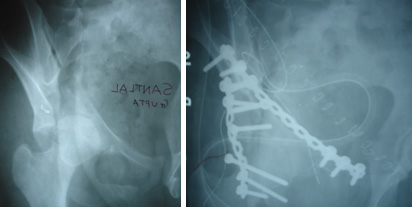

PELVIC & ACETABULAR FRACTURES